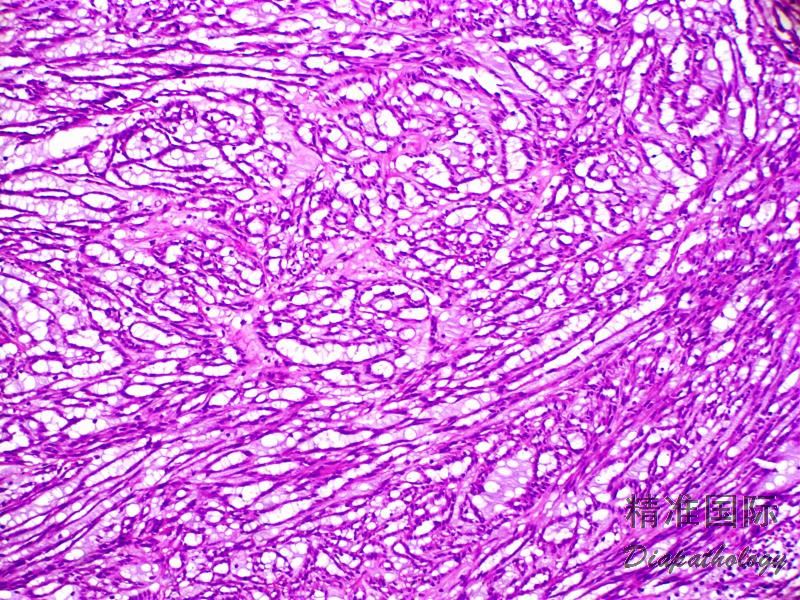

管状癌は乳癌の一種です。これは浸潤性乳管癌 (IDC) のサブタイプです。 IDC は、乳房の乳管内で発生し、その後他の組織に拡大するがんです。管状癌は、腫瘍が顕微鏡で見える管状の構造で構成されていることからその名前が付けられています。腫瘍の大きさは通常 1 cm 以下で、通常はゆっくりと成長します。

管状がんは他の種類の乳がんと非常によく似ているため、医師はこれらの検査を複数要求する可能性があります。生検は、医師が腫瘍の内部を観察して診断を確認するための最良の方法です。あなたの尿細管癌が「純粋」であるか、それとも別のサブタイプの癌と混合しているかを判断するために、複数の検査が必要になる場合もあります。これらすべての情報は、医師があなたにとって最適な治療計画を決定するために必要です。